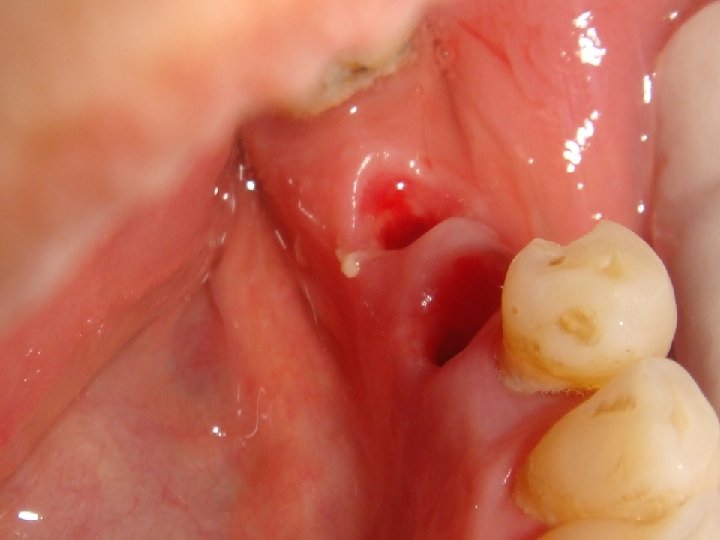

Abstract No. 1: A great challenge in implantology today is a predictable, long lasting red aesthetic result. An innovative treatment concept is based on a non-traumatic and effective shaping of the periimplant soft tissue – including an anatomical shaping from the first second. Especially, too many assembling and removing of abutments can contribute to aesthetic complications by vertical tissue loss. Therefore the “one abutment one time” and the “one crown one time” concepts are preferred. Additionally, platform switched and sealed implant-abutment connection prevent crestal bone loss and an apical shift of mid facial soft tissue.

Abstract No. 1: (cont. . ) In case of a fresh extraction socket the seal with the own tooth or a temporary crown can keep the complete soft tissue shape in a easy and predictable way. This "prosthetic" socket preservation simulates an intentional tooth reimplantation without the root. The same seal and therefore an optimal healing mode of the extraction socket is realized by an immediate implant insertion and restoration.

Abstract No. 1: (cont. . ) The lecture demonstrates a workflow for oral surgeons, prosthodontists and dental technicians to achieve a predictable midfacial soft tissue level by an effective and non traumatic protocol. Primarily results of a prospective clinical trial are promising. Additionally an insight into a scientific based explanatory model is given how a stable conical connection can increase the probability of a periimplant tissue preservation.